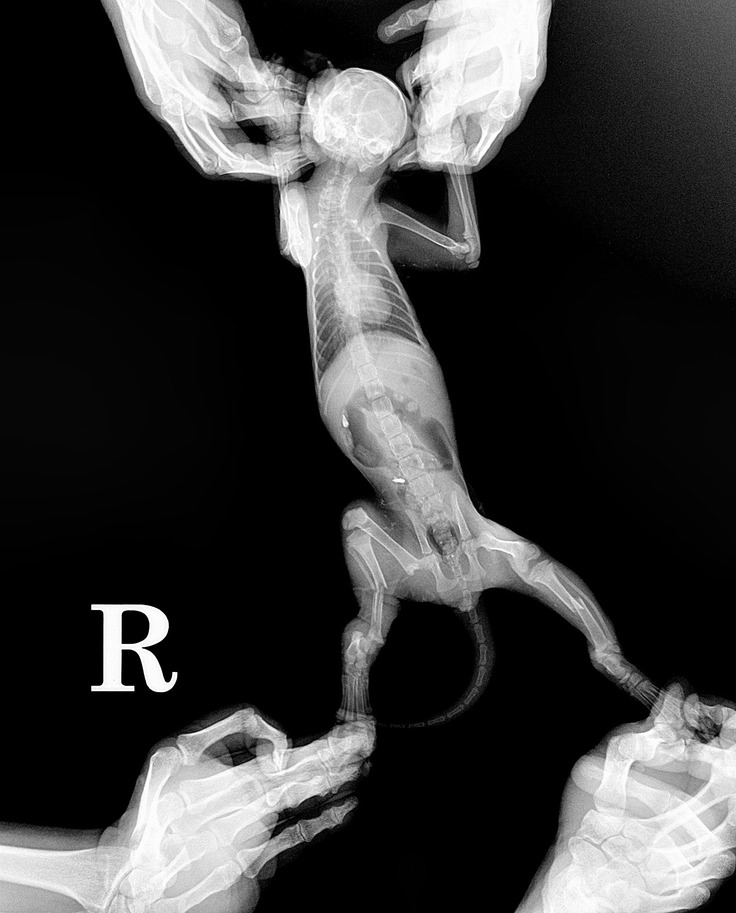

2021年6月19日 交通事故に遭ったと思われる子猫を自宅前で見つけました。

ところが、夜19時になっても母猫が来る様子もなく、ご近所さんと相談し捕獲、夜間救急病院に連れて行きました。カラスにやられていたところもありましたが、なにより交通事故に遭っていて両後肢を骨折し最悪切断する可能性があると先生に言われ、とてもショックを受けました。

翌日、近所の動物病院にて神経はあるので切断する必要がないと言われ、一安心しましたが粉砕骨折をしていて一回の手術では治りきることは不可能と言われました。 カラスにもつつかれた後があり、出血が多く緊急入院することになりました。

交通事故で両後肢骨折した子猫ちゃんの骨折手術費用、血液検査等医療費全般に充てたいと考えております。

手術前

手術後

8月24日にスクリューが皮膚から出ていた為、プレートの除く手術を行いました。

人間で例えると右足首は完治しませんが、歩行には問題がないため再手術は行いませんでした。

●治療・手術対象

猫、雑種、推定2か月、オス

●治療・手術内容

右後肢骨折、左後肢2か所(粉砕骨折・粉砕骨折)